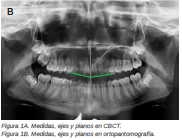

Introducción: La inclusión de caninos tiene una alta incidencia y plantea varias complicaciones clínicas, siendo de vital importancia el diagnóstico precoz y exacto para minimizar los riesgos y complicaciones derivadas. El objetivo de este trabajo es analizar, utilizando como referencia las líneas planteadas por Alqerban, la efectividad de las dos dimensiones en el diagnóstico volumétrico de la inclusión de los caninos maxilares.

Métodos: Seleccionamos 27 pacientes con 36 caninos maxilares incluidos que se realizaron estudio de ortodoncia con ortopantomografía y tomografía computarizada de haz cónico (Cone Beam Computed Tomography, CBCT) del maxilar en la Clínica Universitaria de la Universidad Europea. Se trazaron tres líneas de referencia basándose en la distancia de la cúspide del canino al plano oclusal (L1), a la línea media (L2) y a su lugar ideal de erupción (L3), tanto en la ortopantomografía como en el CBCT. Como valores de referencia ideales seleccionamos un grupo control de 36 caninos maxilares erupcionados.

Resultados: Se compararon los resultados en dos y tres dimensiones mediante la prueba T de Student, tras comprobar su distribución normal mediante la prueba de contraste de Anderson-Darling. No se obtuvo significación estadística (p>0.05) para ninguna de las variables estudiadas.

Conclusiones: El uso del CBCT es vital para asegurar un buen diagnóstico en cuanto a la posición del canino y su relación con estructuras adyacentes y así establecer un plan de tratamiento adecuado. Aun así, la ortopantomografía aporta información suficiente para la planificación inicial.

Radiographic diagnosis of impacted maxillary canines: Comparison between two and three dimensions

Introduction: An impacted canine is a very common condition and raises several clinical complications. Early and exact diagnosis is important in order to minimise the risks and subsequent complications. The objective of this study is to analyse the effectiveness of two dimensions in the volumetric diagnosis for impacted maxillary canines, using the lines proposed by Alqerban as a reference.

Methods: An orthodontic study of the maxilla using orthopantomography with cone beam computed tomography (CBCT) at the Madrid European University Clinic was performed on 27 patients selected with 36 maxillary impacted canines. Three reference lines were drawn based on the distance from the cusp of the canine to the occlusal plane (L1), to the midline (L2) and to its ideal eruption site (L3), in both the orthopanthomography and the CBCT. As ideal reference values, we selected a control group of 36 erupted maxillary canines.

Results: The results were compared in 2 and 3 dimensions using the Student’s t test, after verifying their normal distribution using the Anderson-Darling contrast test. Statistical significance (p > 0.05) was not obtained for any of the variables studied.

Conclusions: The use of CBCT is vital to ensure good diagnosis of the canine position and its relationship with adjacent structures and thus establish an adequate treatment plan. However, orthopantomography provides sufficient information for initial planning.